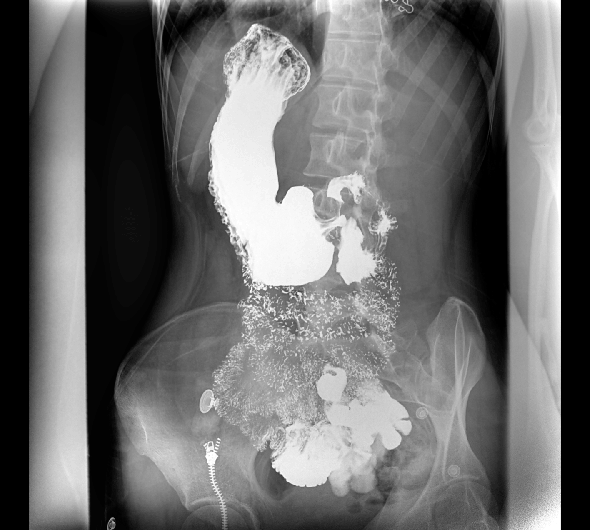

临床图像